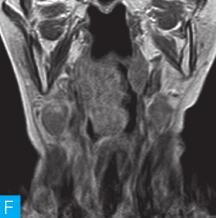

喉咽部MRI检查:病人采取仰卧位,横断位扫描为主,包括T1WI、T2WI及T2WI脂肪抑制序列,扫描范围自鼻咽部至喉咽以下,扫描层厚为3.5mm、层间隔0.35mm,矩阵512×512;辅以冠状位T2WI,矢状位T2WI序列及脂肪抑制序列,平扫后行横断位、冠状位及矢状位的增强扫描,造影剂量0.2ml/kg。见图1。

图1 咽喉部MRI:A.喉咽部MR横断面平扫T1WI;B.喉咽部MR横断面T2WI;C.喉咽部MR横断面T2压脂;D.喉咽部MR横断面增强T1WI;E.喉咽部MR冠状面T2WI;F.咽喉部MR冠状面增强T1WI

MRI平扫可见右侧扁桃体较大的软组织肿块,T1WI呈稍低信号,T2WI呈稍高信号,信号较均匀,T2WI压脂序列上呈高信号,病变与右侧咽扁桃体及舌根部分界不清,左侧咽扁桃体肿大,口咽腔明显变形狭窄,病灶延伸至喉前庭;双侧锁骨上窝及颈血管鞘周围间隙内可见多发大小不等的肿大淋巴结,大部分肿大淋巴结信号较均匀,呈稍高信号,边界清楚,右侧颈部间隙内个别肿大淋巴结内见少量斑片状液化坏死区;增强扫描后下咽部病变及双侧颈部间隙内的肿大淋巴结均呈明显的较均匀强化,提示该两处占位病变的血供较为丰富,且可能为同源性病变,因此采取“一元论”诊断思维进行分析更为合理。

(1)发现病变与认证:扁桃体及颈部病变较为容易发现,主要是分析两方面:一是仔细观察咽部有无原发病变,原发病变的形态及信号;二是评价淋巴结的分布,淋巴结的信号及生长特点。本病例基本征象为扁桃体病变信号均匀,无坏死,颈部淋巴结分布广泛,信号均匀。

(2)定位诊断:对于本病例来说,发现两处病变,包括咽部和颈部。咽部的病变位于扁桃体,延伸至喉咽腔,口咽腔和梨状窝受压变窄。颈部的病变为多发淋巴结增大,淋巴结广泛分布于Ⅱ~Ⅴ区。

本病例的特点为右侧扁桃体肿块,病变边界较清楚,表面光滑,信号均匀。双侧颈部间隙内多发肿大淋巴结,淋巴结围绕颈动脉鞘,部分病变融合倾向,广泛分布于Ⅱ~Ⅴ区,增强后病变较明显强化。

该病例首先对病变进行定位,包括咽部的和颈部的。咽部的病变:病变位于扁桃体,延伸至喉咽腔,口咽腔和梨状窝受压变窄(引起异物感和吞咽困难的原因)。颈部的病变:多发淋巴结增大,淋巴结广泛分布于Ⅱ~Ⅴ区。扁桃体病变的信号特征:扁桃体病变表面光滑,提示黏膜完整,病变来源于黏膜下,病变信号均匀,无坏死,进一步支持病变来源于黏膜下。颈部淋巴结病变的特征:淋巴结分布广泛,信号均匀(可以初步排除结核和转移,后两者容易坏死),围绕颈动脉鞘,但是不侵犯颈动脉鞘(转移容易侵犯颈动脉鞘),部分淋巴结融合倾向(结核淋巴结增大,无融合倾向,而且容易坏死),病变中度强化,进一步支持颈部淋巴瘤的诊断。诊断原则:首先仔细观察咽部有无原发病变,原发病变的形态及信号,尤其黏膜是否完整。其次评价淋巴结的分布,淋巴结的信号及生长特点。